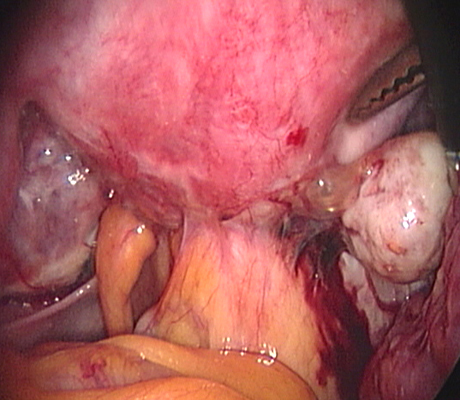

Endometriosis is a non-cancerous condition where the endometrial tissue or womb lining which normally grows only in the uterus is found in other parts of your pelvis, for example the ovaries, fallopian tubes, rectum, bladder, appendix and pelvic walls. This womb lining that grows outside the uterus responds also to hormones but at the time of your periods it can not be expelled (as the womb lining) and causes pain, cysts in the ovaries (called chocolate cysts), inflammation in your pelvis, scar tissue, pain with sexual intercourse, chronic pelvic pain, pain when passing bowel motions, lower backache, symptoms similar to urinary tract infections, premenstrual discomfort, etc.

Laparoscopy is an operation (keyhole surgery) conducted under general anaesthesia. A telescope is introduced into a small incision in your navel, other small incisions are made for using special laparoscopic instruments and all the pelvic organs are examined with magnification (Video-laparoscopy) ; then the endometriosis is treated. Video Laparoscopy allows conservative surgery (hysterectomy is NOT the usual treatment for endometriosis) which means laparoscopic excision of the endometriotic implants, with restoration of the normal anatomy and preservation of the uterus, tubes and ovaries.

There are a number of ways as endometriosis may cause infertility. Although women with mild endometriosis may get pregnant, endometriosis is usually a progressive disease, as it gets worse with time. So early diagnosis and treatment is important. Women with advanced disease have low chance of achieving a spontaneous pregnancy. There is plenty of evidence based medicine showing that laparoscopic treatment of endometriosis does improve fertility. When a patient has an ovarian endometriotic cyst associated with infertility, laparoscopic surgery is the first line of treatment. The average pregnancy rate reported after surgery in these cases is 35-50%. So laparoscopic surgery provides a woman with good chances of becoming pregnant spontaneously.